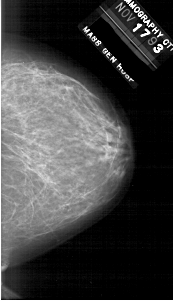

A_1915_1.RIGHT_MLO

RIGHT_MLO LINES 6406 PIXELS_PER_LINE 3121 BITS_PER_PIXEL 12 RESOLUTION 43.5 NON_OVERLAY